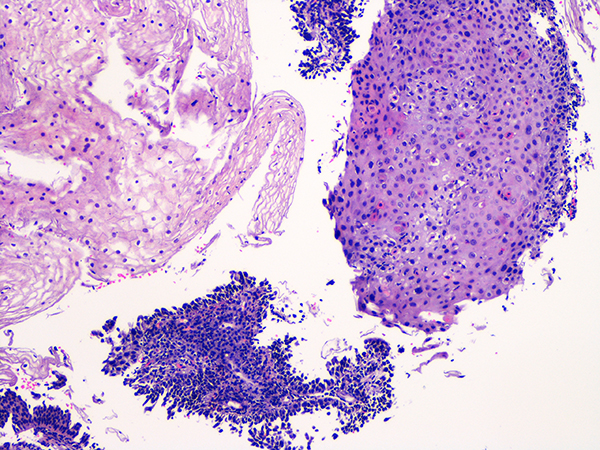

Soft Bx CIN 2 10x - Low Power |

![]() Case 2

Soft Bx CIN 2

40x - High Power